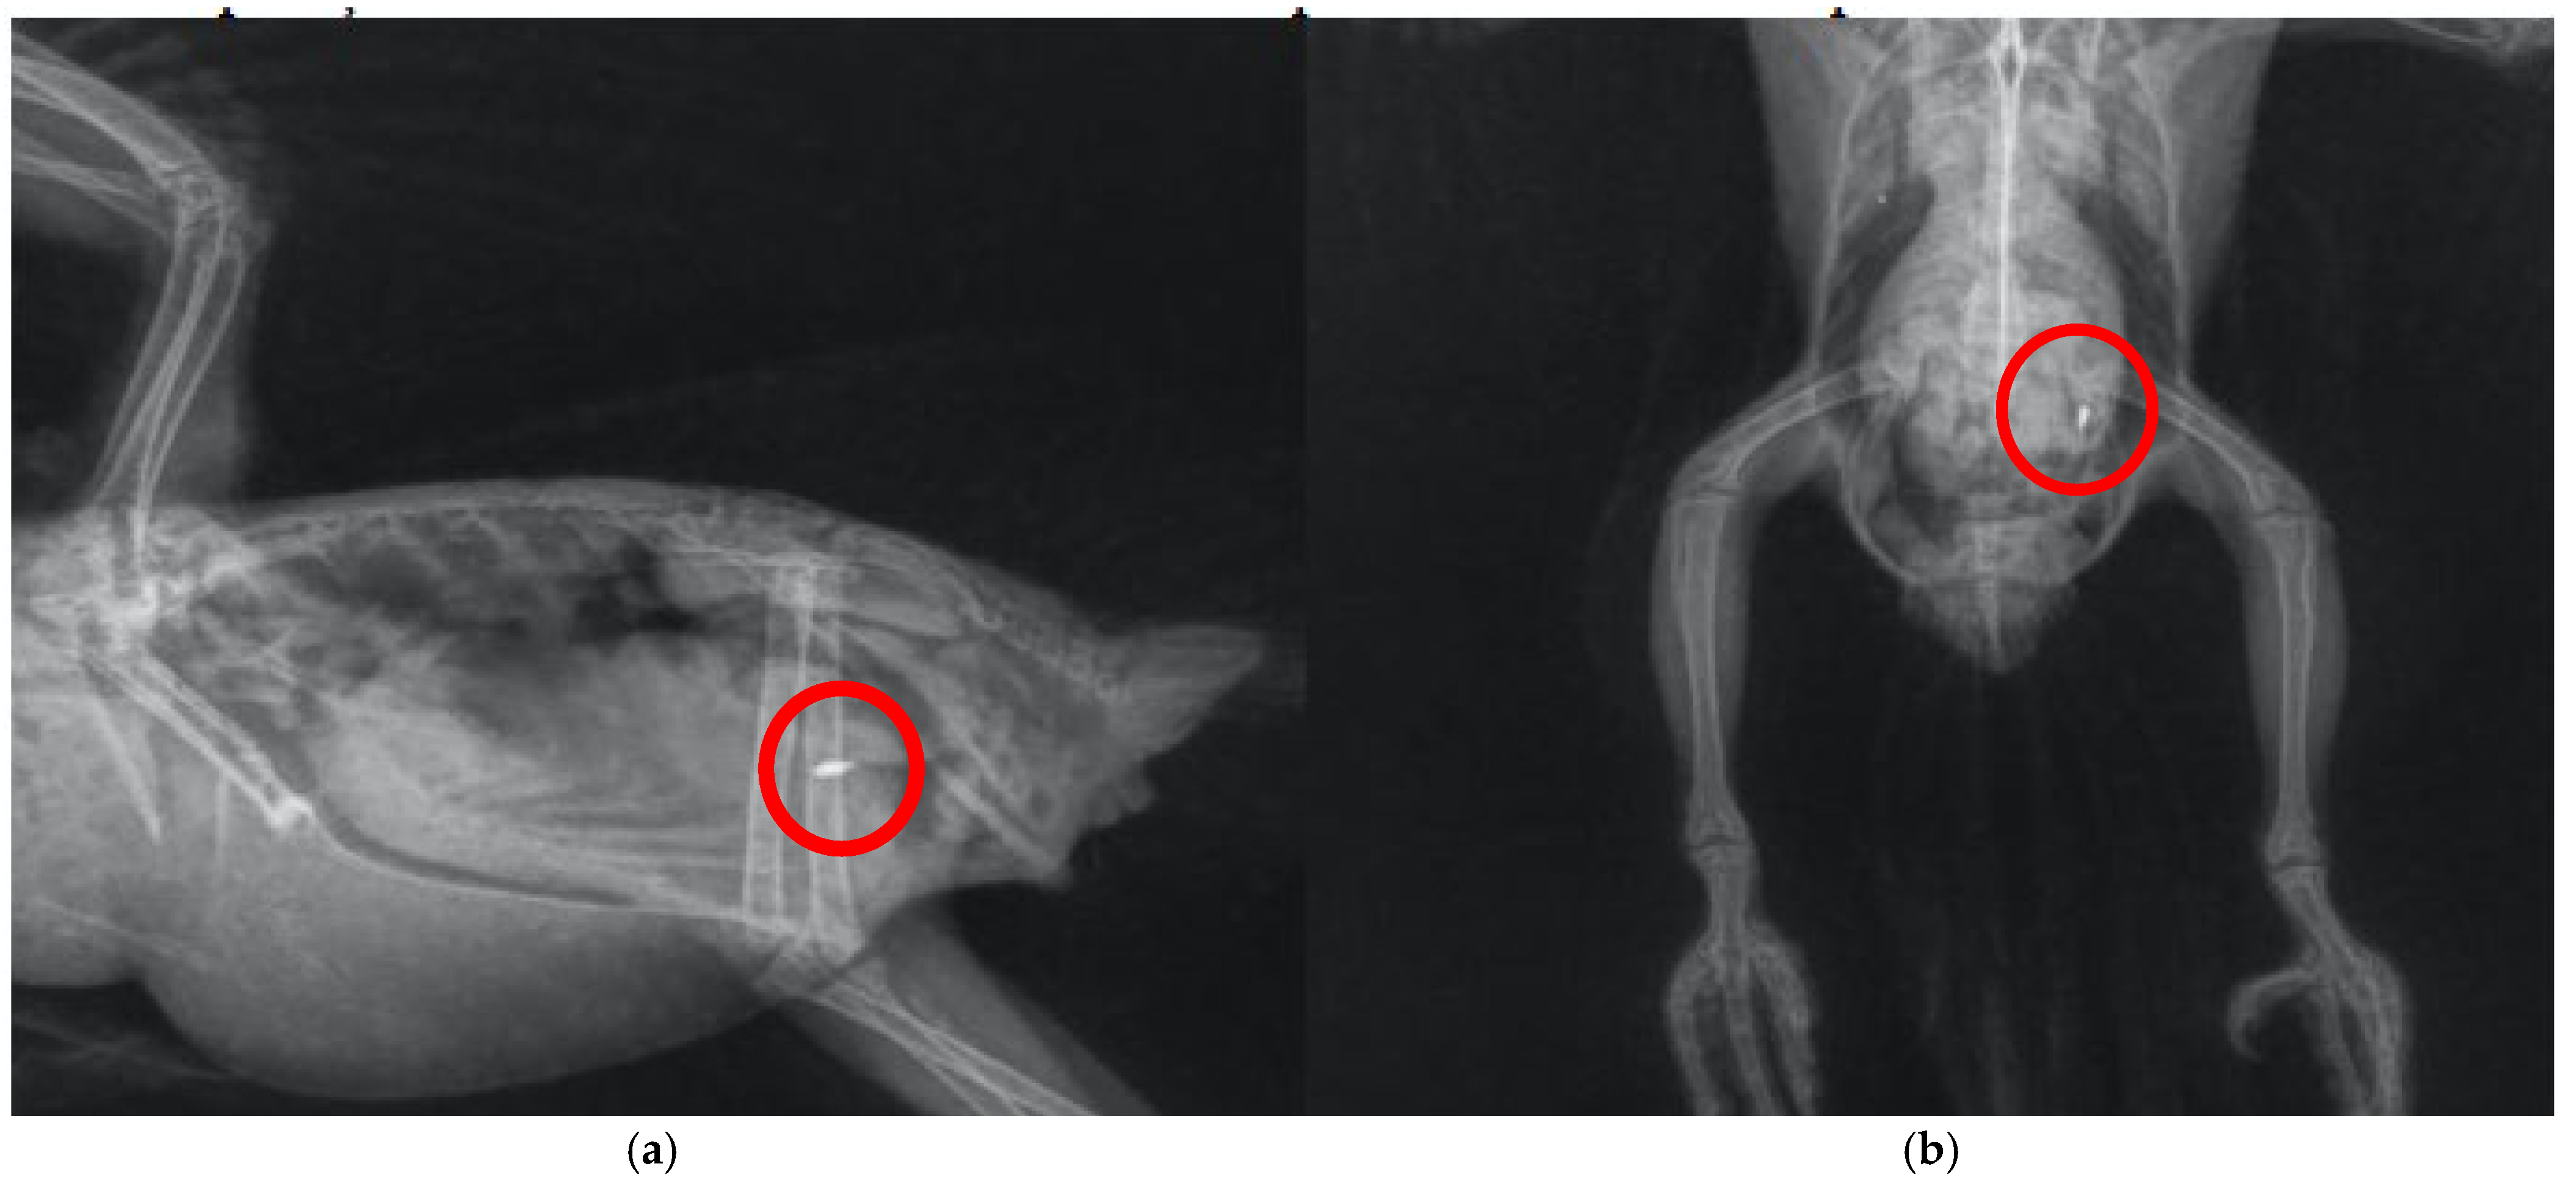

Specimens of Aratinga jandaya voluntarily surrendered and treated at the Wildlife Sector of the Veterinary Hospital (HVSAS) at the Federal University of Pará (UFPA), in Castanhal/PA, exhibited symptoms (regurgitation, apathy, and disoriented behavior) of heavy metal poisoning, possibly Hg and/or Zn, and the presence of a radiopaque foreign body in the celomic cavity radiographic exam suggestive of portions of the gastrointestinal tract (Figure 1). After symptomatic generalist treatment (Ca-EDTA 70 mg/kg PO, BID for 7 days, fluid therapy with lactated Ringer’s, vitamin supplementation with complex B and omega-3, and nebulization), the animals improved, indicating the possibility of intoxication and raising awareness of the potential contact of these individuals with metals in peri-urban and urban areas where the presence of this and other psittacids species is growing (Figure 2). Although radiographic findings and clinical signs strongly supported metal ingestion, the exact nature of the metallic material was not confirmed via residue analysis. Therefore, differential diagnoses such as mycotoxicosis, organophosphate exposure, or chronic intoxication by environmental zinc particularly in urban-adapted psittacids cannot be ruled out and may present with overlapping symptoms that also respond to chelation and supportive therapies [10,21,30].

Figure 1. Radiographic exam of the celomic cavity of Arantiga jandaya. (a) Ventrodorsal projection—The heart and liver form a typical hourglass structure, with radiopacity of the pulmonary field; dilated ventriculus and proventriculus; radiopaque structures (outlined in red) in the ventriculus region, suggestive of metallic content. (b) Right lateral-lateral projection—Presence of radiopaque foreign bodies (outlined in red), also suggestive of metal. (Personal archive).